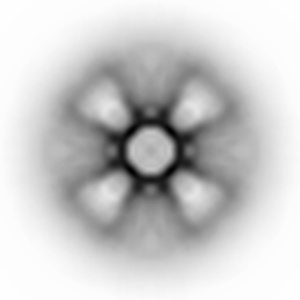

Negative-stain EM reconstruction of SpFN_1B-06-PL, a SARS-CoV-2 spike fused to H.pylori ferritin nanoparticle vaccine candidate

Single-particle30.0 Å